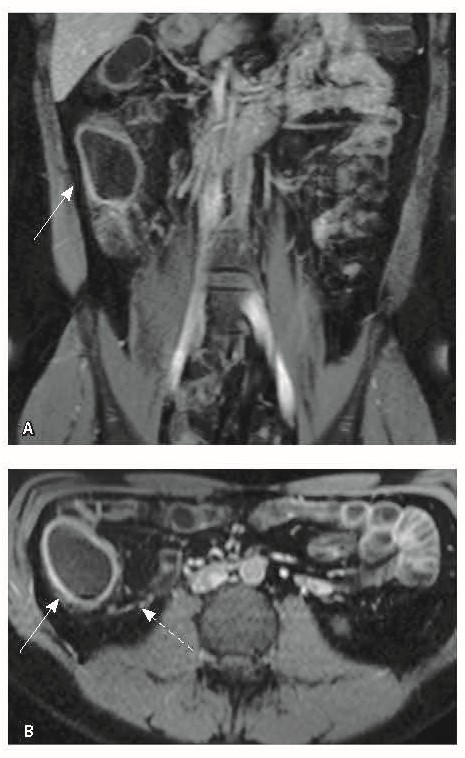

Назначена ГИБТ адалимумабом (препарат Хумира) по стандартной схеме 160 мг п/к (неделя 0), 80 мг п/к (неделя 2) с последующим плановым поддерживающим режимом 40 мг п/к каждые 2 недели. Через 9 месяцев установлена эндоскопическая ремиссия, однако сохранялась концентрация фекального кальпротектина более 2000 мкг/г. Через год жалобы возобновились, тогда же впервые была выявлена задняя анальная трещина. Выполнена магнитно-резонансная энтерография, обнаружены воспалительные изменения, характерные для БК (рис. 2 и 3).

Рис. 2. Магнитно-резонансная энтерография, Т2-взвешенное изображение: А, В – фронтальная проекция; Б – аксиальная проекция. Наблюдается отсутствие гаустрации в восходящем отделе ободочной кишки, утолщение ее стенки до 5 мм (стрелка), снижение магнитно-резонансного сигнала от прилежащих отделов клетчатки, ее неоднородность (пунктирная стрелка), увеличение лимфатических узлов до 6 см в диаметре по ходу сигмовидной кишки (стрелки)

Рис. 3. Магнитно-резонансная энтерография, Т1-взвешенное изображение после внутривенного контрастного усиления (гадобутрол, 5 мл): А – фронтальная проекция, Б – аксиальная проекция. Наблюдается выраженное усиление интенсивности сигнала от восходящего отдела ободочной кишки (стрелка), усиление сигнала от окружающей клетчатки (пунктирная стрелка)